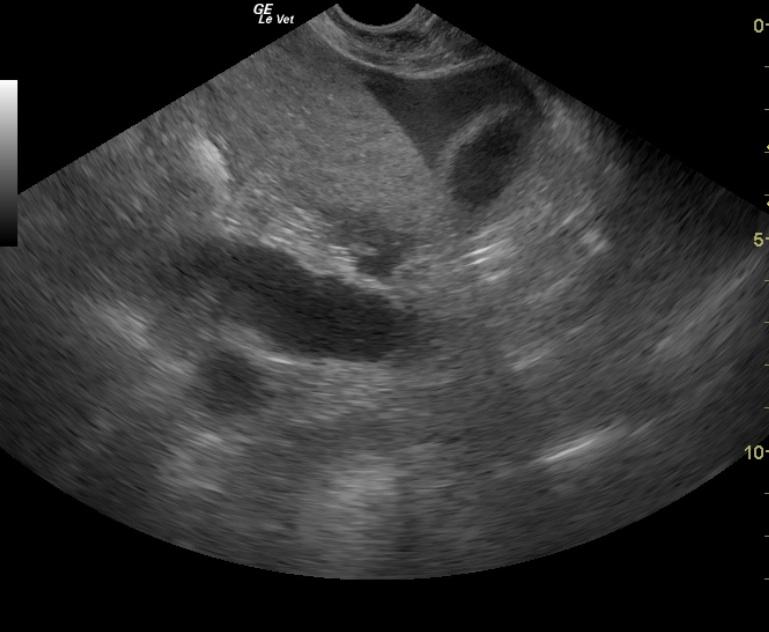

The abdomen in this patient presented a moderate amount of mildly echogenic free fluid, which was found to be hemorrhagic modified transudate on abdominocentesis. The uterus was dilated and irregular. This is consistent with pyometra with some omental reactivity. Rupture could not be ruled out given the hemorrhagic modified transudate free fluid.

Pyometra. Undefined hemorrhagic free fluid in the abdomen.

Pyometra. Undefined hemorrhagic free fluid in the abdomen. Potential underlying immune mediated disease or neoplasia given the anemia.